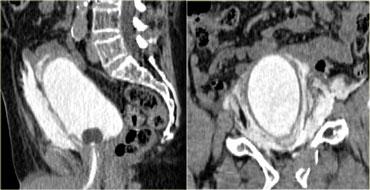

Bên trái là hình ảnh của một nam giới 65 tuổi bị xe ô tô đâm ở tốc độ vừa phải.

Mất ý thức trong 2 phút.

Đặt thông tiểu Foley và phát hiện đái máu đại thể.

Phim X-quang cho thấy gãy xương mu di lệch vừa với các mảnh xương nhọn ở vùng bàng quang.

Bên trái là hình ảnh CT chấn thương thường quy.

Nhận xét các dấu hiệu hình ảnh?

Có hình ảnh gãy xương chậu di lệch với một mảnh xương nhọn hướng về phía bàng quang.

Có dịch trong khoang trước bàng quang (khoang Retzius).

Bên trái là hình ảnh trước và sau khi chụp CT bàng quang cản quang.

Có thuốc cản quang trong lòng bàng quang bao quanh ống thông Foley và có hiện tượng thoát thuốc cản quang vào khoang trước bàng quang hay khoang Retzius.

Hình ảnh này được gọi là ‘dấu hiệu răng hàm’ (molar tooth sign), gợi ý vỡ bàng quang ngoài phúc mạc.

Bên trái là tái tạo mặt phẳng đứng dọc và đứng ngang.

Lưu ý không có thuốc cản quang lan vào rãnh cạnh đại tràng, do đó không có sự lan rộng vào trong phúc mạc.